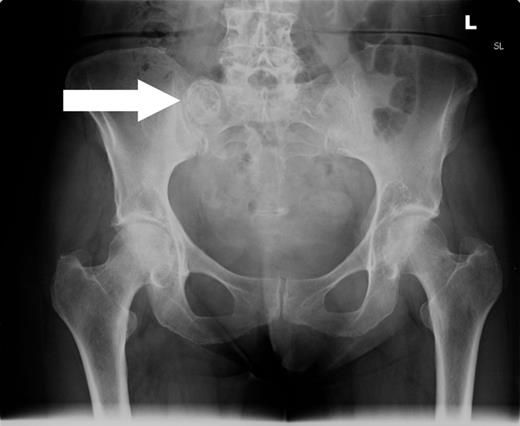

She subsequently had a colonoscopy, which revealed mild sigmoid diverticulosis and no mass lesions. The caecum appeared distorted by a large faecolith impacted in the appendiceal orifice. This was visible as an ovoid calcified lesion projected over the right sacral ala on a radiograph (Fig. 1) of the pelvis. A computed tomogram (Fig. 2) of the abdomen and pelvis demonstrated a giant calcified appendicolith, measuring 2.5 cm in its largest dimension, within the base of an otherwise normal appendix. Uncomplicated sigmoid diverticulosis was also noted.

Anterior–posterior radiograph of the pelvis demonstrating a calcified ovoid lesion projected over the right sacral ala.